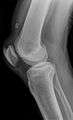

X-ray of a tear of the patellar tendon. On the left: The kneecap is pulled up. On the right: Significant dent in the soft tissue above the kneecap.

Operative image: 1. Kneecap 2. upper patella pole with drill holes 3. Stump of the quadriceps tendon